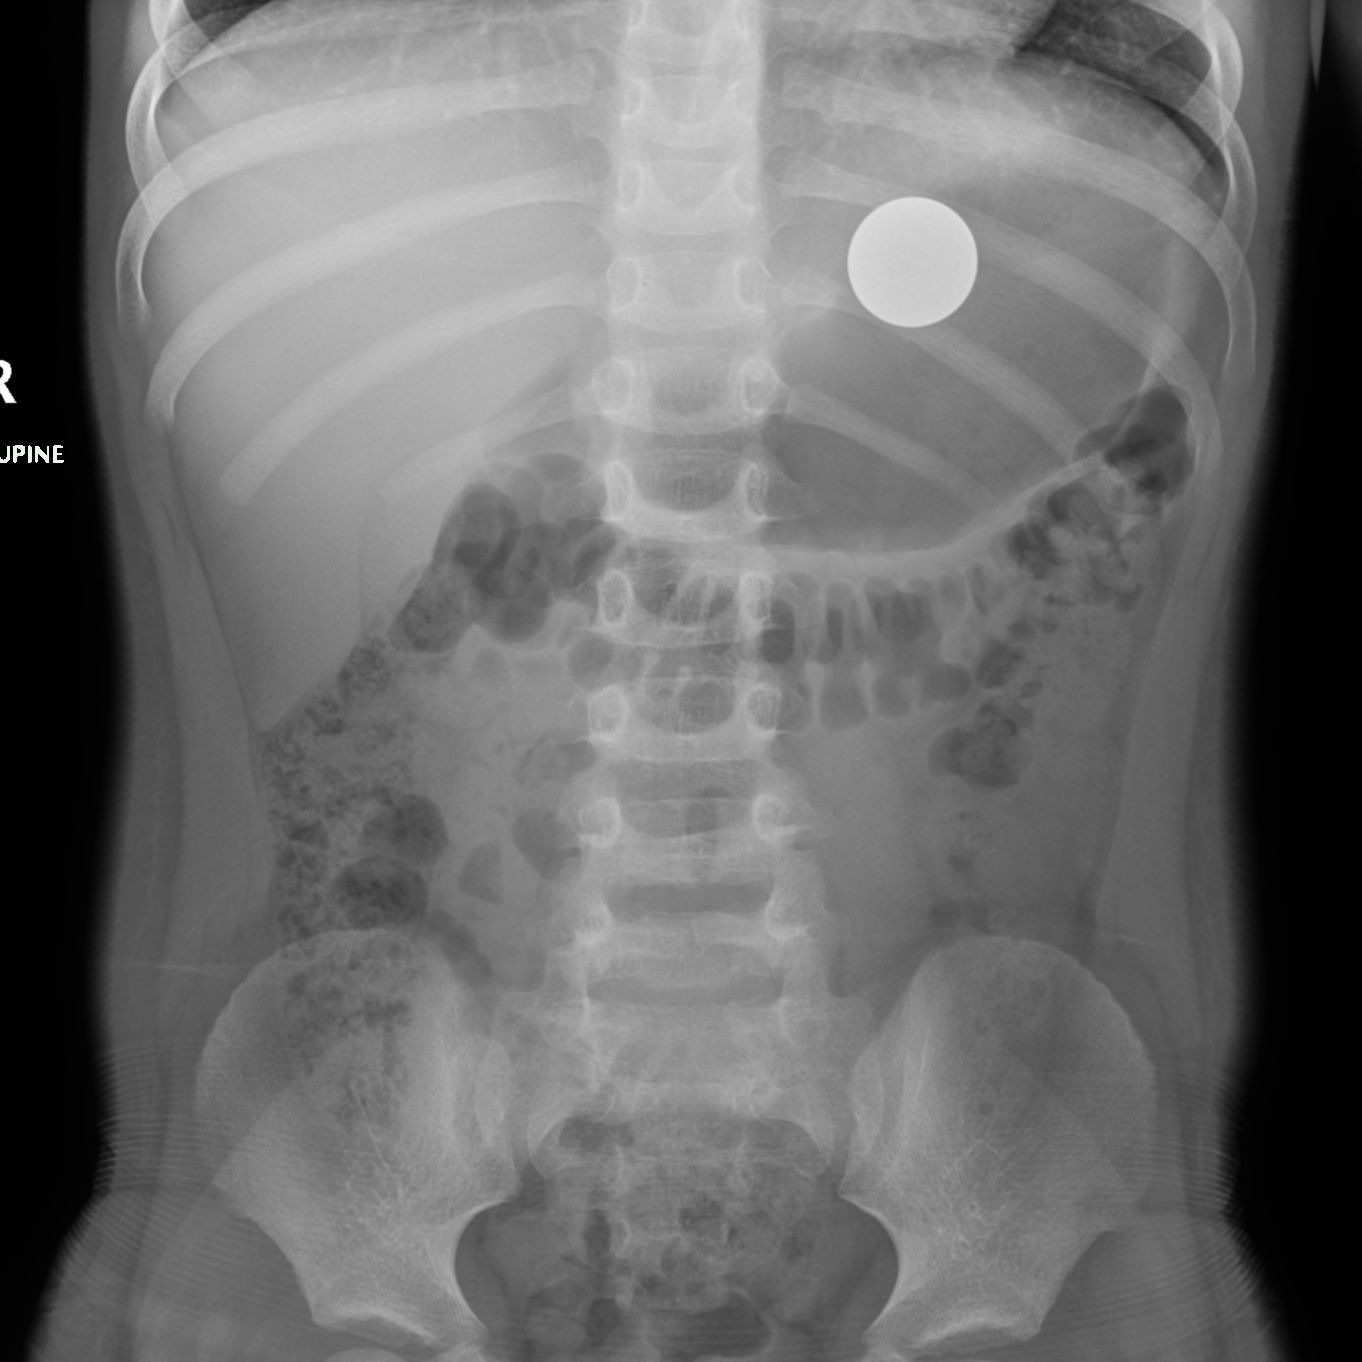

Em algumas condições, a localização exata da alteração é fundamental para tomada de conduta.

Como, por exemplo, em uma criança de 5 anos que acabou de engolir uma moeda. Qual especialista deve ser chamado para avaliar este caso? O cirurgião torácico? O cirurgião gastro? Para responder esta pergunta, devemos localizar onde a moeda está localizada.

A radiografia obtida do paciente demonstra que a moeda (imagem ovalada, com densidade de metal) está localizada no estômago. Com esta informação, podemos prosseguir na condução do caso.

Este caso é um exemplo de como os exames de imagem podem ser utilizados para localização de uma lesão ou uma alteração, auxiliando nas tomadas de decisão.